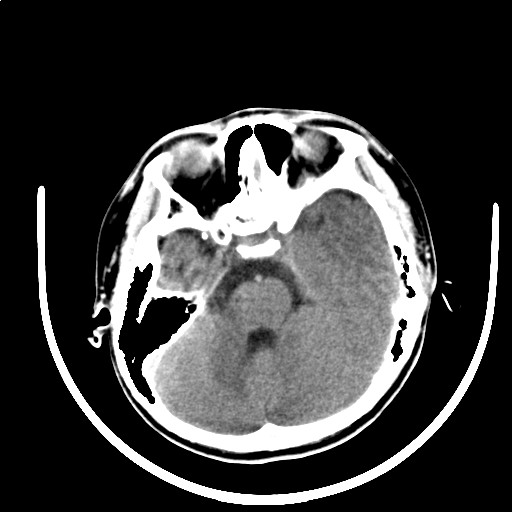

标题: PED3416:F,12Y,智力下降,学习成绩差,8个月时发过高烧。

右侧大脑发育不良伴动静脉畸形。

右侧半球萎缩,软化,多量脑回样钙化,考虑颅面血管瘤病,建议dsa检查

右侧半球萎缩,软化,多量脑回样钙化,同侧颅盖板障增宽,考虑颅面血管瘤病,建议dsa检查与化脓性脑膜炎后遗改变鉴别。